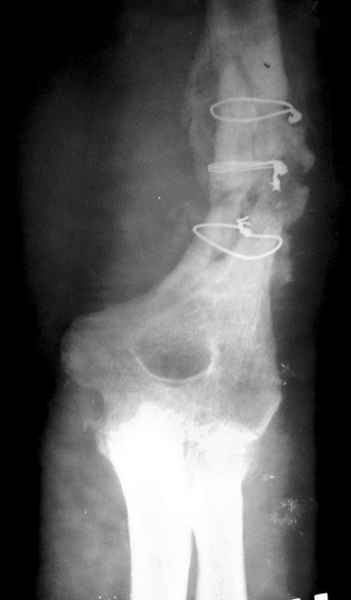

На примере два случая, извиняюсь за качество снимков, снимки и случаи из бывшего союза.

Первая больная с "успехом" была прооперирована 6 раз различными методами открытого и закрытого

остеосинтеза, включая то, что в Кисловодске заезжим австралийским "кудесником" на ложный сустав уложена скорлупа от страусиновых яиц. Последняя операция одиноким локинг плейт в одной из клиник.

Через год по поводу тех же проблем сделали ревизию, оригинальную пластину оставили как есть, только укрепили добавлением еще одной пластины и сделали костную пластику.

Через два месяца увидели признаки консолидации.

Второй случай, также после множественных операций:

пластина, аппарат, серкляж и парез нерва.